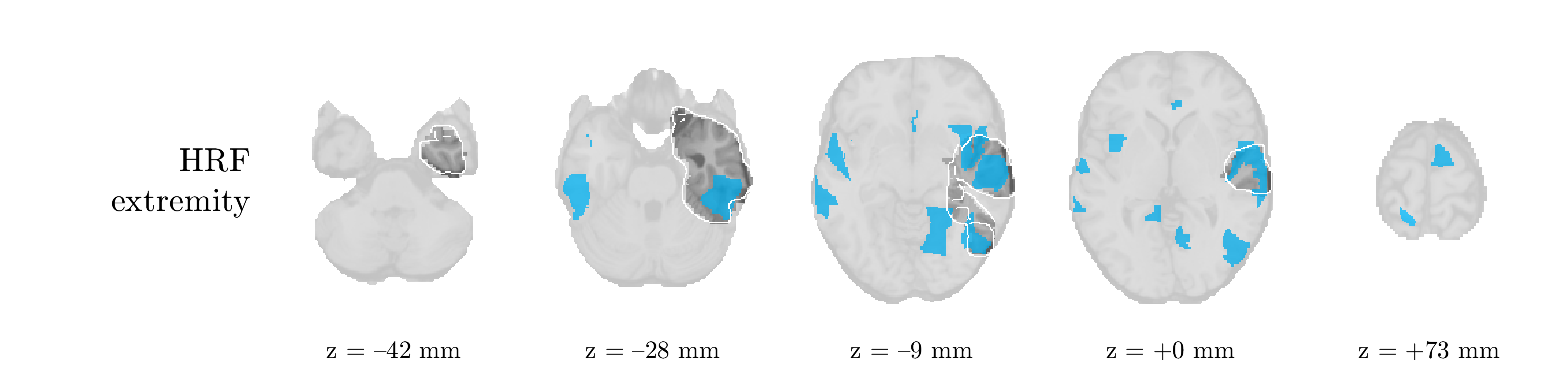

We analyze the solution with sources. Figure 1 shows the EEG signatures and HRF waveforms. One of the sources is highly correlated to the MWF reference (in grey), which was already known from Table B.3. This IED-related source had a typical low-frequency spectrum, which is expected for the typical spike-and-wave interictal discharges. The topography is relatively diffuse, although the highest amplitudes are mostly in the left hemisphere. This is in accordance with the lateralization of ictal onset zone (left temporal lobe, cfr. Table 1). There are some noteworthy observations to be made about some of the other components. The fourth has an unusually sharp spectrum, is mainly localized on two nonadjacent center electrodes, and is sustained for a single period of many seconds Hence, this component likely captured an artifact (of yet unknown origin), although we spotted no large-amplitude changes in the EEG itself. Similarly, the third source is only present at one frontal electrode, and exists in a frequency range above 20 Hz. It might represent a muscle artifact, e.g., due to frowning or twitching of some muscles in the forehead. The HRFs of all ROIs are shown in Figure 1(b). Two of the basis functions seem to have converged to a very similar waveform, which is an unfortunate possibility if two initial HRFs are too close to the same local optimum in their respective parameters. This reduces the expressive power of the basis set, which is clearly visible, since many ROIs have a nearly identical HRF. One of the twenty ROIs with the highest-entropy HRF overlapped the IOZ, although clearly this HRF (bold line) is not among the most dissimilar waveforms for this patient. This is also visible in Figure 2: both the HRF entropy and extremity maps show a small overlap with the delineated IOZ. Despite the good correspondence in the EEG domain, no significant (de)activation of the IED-component is found inside the IOZ.

We analyze the solution with sources, and show the results in Figure 3 and 4. As for patient 1, we found a source which is strongly correlated to the MWF envelope, and which had a mostly low-frequency behavior characteristic for spikes. The topography is mostly uninformative, and does not clearly correspond to the patient’s clinical data. The third source is mostly present at both sides of the head, is very sparsely active in time, and has a high-frequency content: this is most likely an artifact due to the neck muscles. Again, there is one of the highest-entropy HRFs which belongs to a ROI in the IOZ. Now, the waveform is clearly resolved from the other HRFs, through the strong initial dip (before 0 seconds). Such a dip is sometimes observed in HRFs, but its underlying physiological mechanism is not yet fully understood. It is possible that this dip reflects altered vascular autoregulation near the IOZ (cfr. the explanation in the Section 1 of the main text), or a rapid depletion in oxygen due to IED generation (before the IED becomes visible on the EEG). Figure 4 furthermore shows that the IED-related component is significantly active in parts of the IOZ, and deactive in others. As mentioned earlier, this deactivation may or may not be due to errors in sign correction. Interestingly, the ROI with the high alteration in neurovascular coupling is distinct from both the activated and deactivated ROIs.

We analyzed the solution with sources, and show the results in Figure 5 and 6. There is one source which is mostly correlated to the reference (but not extremely, see also Table B.3). This source had a right-temporal focus, conform the diagnosis in Table 1. The second source illustrates the phenomenon of an erroneous sign exchange between the spatial and spectral profiles. Also one of the HRFs has a negative polarity, which is a failure of the sign correction procedure (in this case, because there is exceptionally no positive overshoot). However, the HRF variability metrics are still interpretable, and indeed two ROIs among the ones with the highest-entropy HRFs overlap with the IOZ. The IED component is significantly active in a tiny portion of the IOZ (cfr. Figure 6). The second source is significantly active in symmetrical parts of the parietal lobe. Given its ongoing fluctuation over time, we hypothesize that this source captures a resting state network (RSN).

We analyze the solution with sources, and show the results in Figure 7 and 8. There is a clear IED-related component, with a very high correlation to the MWF reference, a typical spectrum, and an anterior-temporal focus, which corresponds very well to the patient’s diagnosis (cfr. Table 1). The fifth source seems present at only one channel, and has spectral harmonic at Hz and Hz. One of these peaks is reminiscent of the fourth component in patient 1. As Figure 8 shows, the HRF entropy and extremity prove to be strong biomarkers for the IOZ in this case, and also the significant IED activation and deactivation allow correct localization. In Figure 7, it is clear that some HRFs may still have the wrong sign, which means that the interpretation of ‘active’ and ‘deactivated’ is flipped in those ROIs. Hence, regions of significant deactivation are in fact significantly activated. The fourth source had a significant overlap with the auditory RSN, and its spectrum reveals activity in the band.

We analyze the solution with sources, and show the results in Figure 9 and 10. One source is strongly correlated to the MWF, while the other source is likely an artifact, given its very sparse temporal profile. Both sources coincide at one high-amplitude peak, by which we infer that this is probably an artifactual period in the signal. Indeed, when inspecting the original EEG signals, we found high-frequency muscle artifacts at these times. This source also had no significant activation in its spatial map, which corroborates its non-neuronal origin. The IED-related source had a broader spectrum than most other cases, and an uninformative topography. None of the ROIs with high-entropy HRFs is located in the IOZ. The pseudo t-map provides correct localization of the IOZ, however.

We analyze the solution with sources, and show the results in Figure 11 and 12. We found a clear IED-related component, with a characteristic spectrum and a topography which is backed up by the patient’s diagnosis (left anterior-temporal IOZ). The fourth source has a very similar topography and spectrum to the fifth source in patient 5. One HRF inside the IOZ had a high-entropy, and is distinguishable from the others by its very sluggish waveform, i.e., it is smeared out in time, with no sharp over- or undershoot. Also the pseudo t-map provided an accurate localization of the IOZ. Notably, in this patient, the extremity metric misses the deviating HRF in the IOZ (while the entropy metric picks it up). The second source overlapped with the frontal part of the default mode network (DMN), and is active in the and low bands.

We analyze the solution with sources, and show the results in Figure 13 and 14. We found two components which had correlated time courses. At the time of the peaks, we found higher-amplitude events in the EEG with dubious origin, hence they may or may not be artifacts. One of both components is more strongly correlated to the MWF, and its activation is concordant with the IOZ. The second component shows high overlap with the sensorimotor network. For this patient, none of the IOZ’s ROIs had extreme values of either HRF metric.

We analyze the solution with sources, and show the results in Figure 15 and 16. In this patient, there is only a moderate correlation of a component with the MWF reference time course. This component’s topography (left occipital) agrees with the clinical description, however. The HRF extremity (and not the entropy) is high in a small part of the IOZ. Both the significant IED activation and deactivation allow correct localization as well. The second source seemingly captured high-frequency oscillatory activity in the sensorimotor network, similar to the previous patient.

We analyze the solution with sources, and show the results in Figure 17 and 18. The IED-related source had a high correlation with the MWF reference, but an odd bimodal spectrum. Its EEG topography is very consistent with the clinical description. Both HRF extremity and entropy are useful biomarkers for the IOZ. The IED activation and deactivation maps each had a very small overlap with the IOZ. The second source is temporally sparse and captures high-frequency EEG variations, which we identified as muscle artifacts.

We analyze the solution with sources, and show the results in Figure 19 and 20. Again we observe an IED-related source and a seemingly artifactual source with a spectral peak near 34 Hz. Many of the high-entropy HRFs are highly noncausal, and are associated to ROIs inside the IOZ. Hence, with both HRF metrics, the highest-scoring ROIs provides good localization of the HRF. While there are no significantly active ROIs in the IOZ, there are several significantly deactivated ROIs, which may indicate that the sign standardization was not done flawlessly (cfr. also some of the negative-peaking HRFs for patient 10). Surprisingly, the second source had one significantly active ROI, which overlaps with the IOZ, but which did not match its EEG topography. Hence, the nature of this source remains ambiguous.